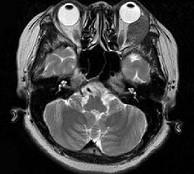

问题 女,52岁,左眼球突出二十余年, T3、T4均正常,影像检查如图所示,应诊断为 ( )

选项 A、血管瘤 B、炎性假瘤 C、脂肪瘤 D、畸胎瘤 E、错构瘤

答案 E